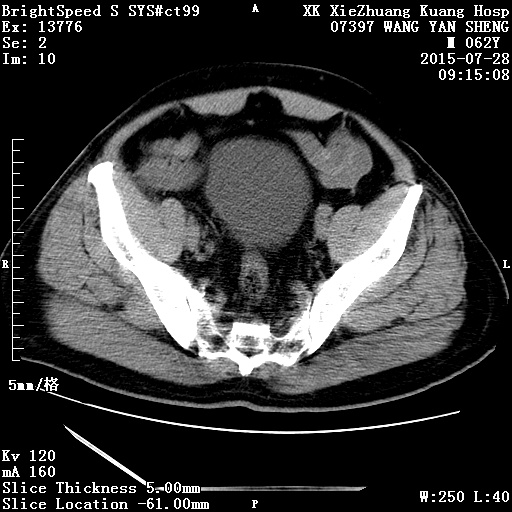

CT50920:膀胱

本帖最后由 cefcmj 于 2015-7-28 15:36 编辑 前列腺肥大入院。无其他症状。

膀胱镜、病理:炎性肉芽肿

1)后尿道结石。2)右侧输尿管末段管壁增厚,膀胱右后壁(相当于右侧输尿管入膀胱处)亦增厚;考虑为炎性改变。建议必要时行膀胱镜检查排除肿瘤性病变。

前列腺增生 肥大 硬化。